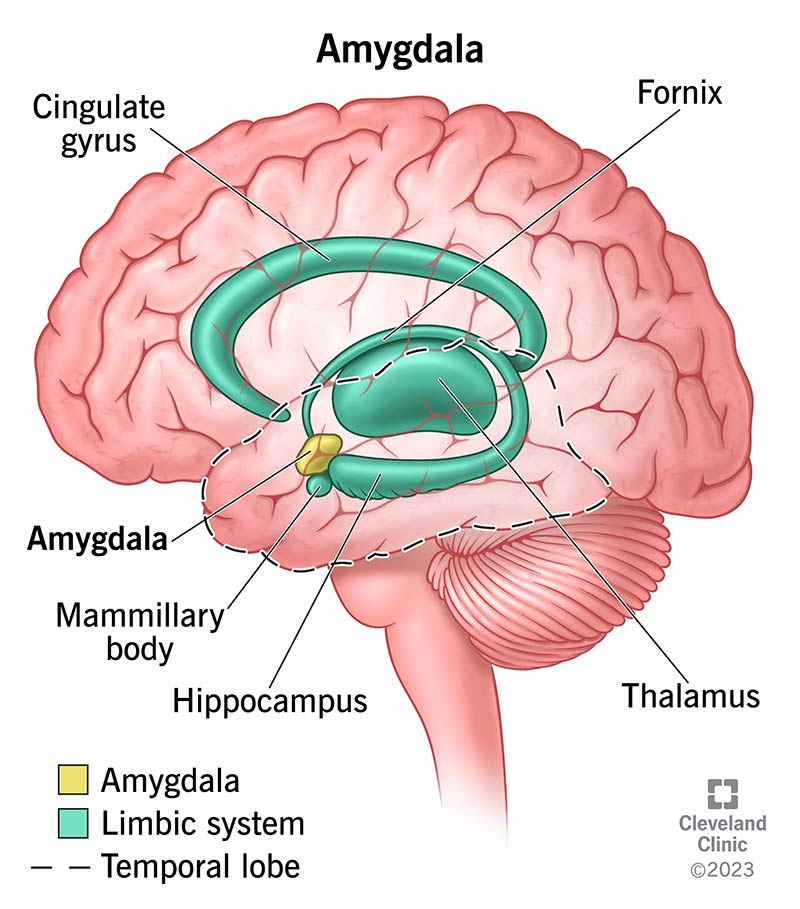

Amygdala: What It Is and What It Controls

Know Your Brain: Amygdala

Damage to the Amygdala: Functions, Symptoms, & Treatments

Amygdala Function and Location

Limbic System: Amygdala (Section 4, Chapter 6) Neuroscience Online

Amygdala's Location and Function

Amygdala - The Science of Psychotherapy

Amygdala: Anatomy, Location, and Function

Amygdala | Facts, Position In Brain, Summary & Function

Limbic System: Amygdala (Section 4, Chapter 6) Neuroscience Online

The Limbic System